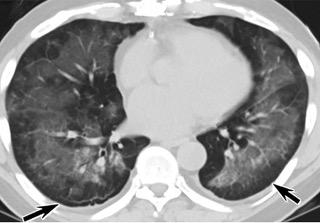

中、下肺轴位CT平扫显示毛玻璃样混浊伴胸膜下保留(箭头)。(同一病人CT影像)

16位被文献报道为电子烟肺炎的患者被专家判定为“病毒性感染”,即有可能是新冠肺炎的“疑诊患者”,其中更有5位临床症状和治疗情况相对完整的患者被判定为“中度可疑”。因此在2019年美国报道的电子烟肺炎中存在病毒性感染的病例,而且不排除美国电子烟肺炎中存在新冠肺炎的可能性。